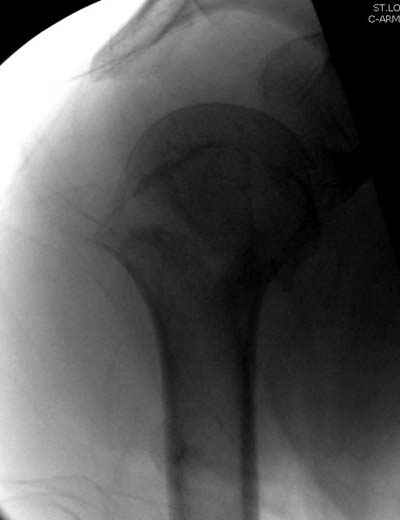

Да. У нас довольно скромный опыт такого остеосинтеза (по 2 случая - плечо и наружная лодыжка), дошли до использования самого простецкого троакара, через который мы сверлим кость и вводим 6 мм стержни, когда накладываем аппарат. Соответственно, в качестве забойника отлично работает любой стержень от аппарата Илизарова. Еще из наших туземных особенностей - страшная любовь к спицевым дистракторам, поэтому делали в нем. Результат у этой дамы неизвестен, т.к. она из области и уехала рожать сразу после остеосинтеза, сейчас прошло больше 5 месяцев...

Что-то, наверно, сделали мы не совсем оптимально, поскольку у Анатолия Федровича и его соратников как-то красивее "раскрываются" спицы в головке плеча - надеюсь, он прокомментирует и подскажет, что надо подправить.